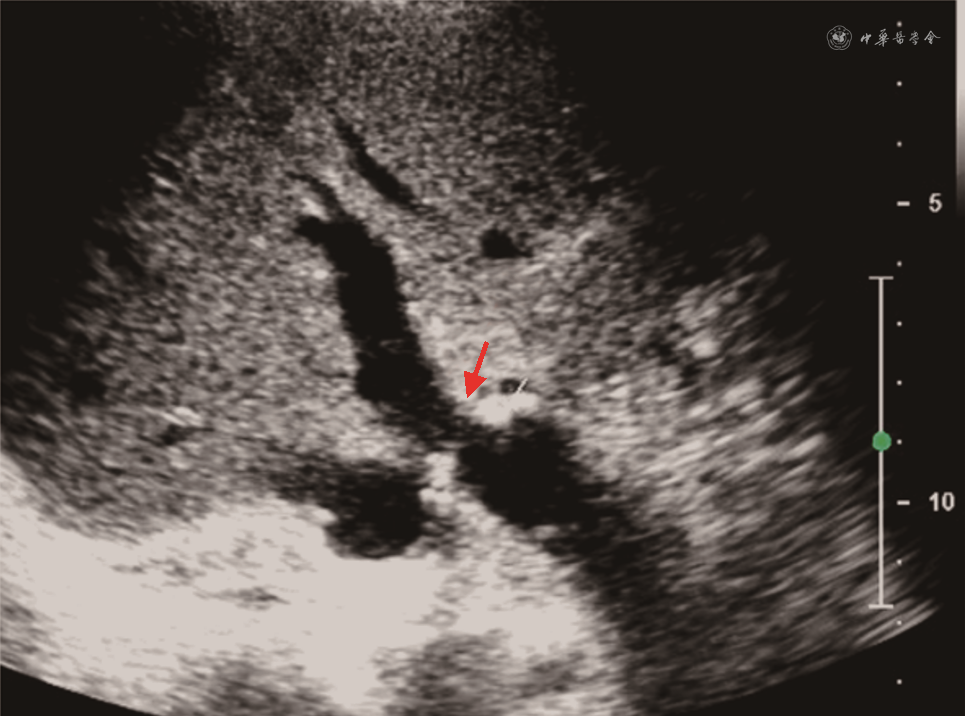

(1)HAT:HAT发生率为4%~12%,是肝移植术后最常见的肝动脉并发症,占移植后血管并发症60%。HAT的中位发生时间是移植后6.9 d[49, 50],约70%发生在吻合口。CDFI是目前筛查HAT的首选方法,在肝门、肝内外均未测及肝动脉血流,高度提示HAT[51]。CDFI诊断HAT的准确度60%~92%,移植后早期肝脏肿胀、肝动脉内径细小(1~3 mm)及术后血管痉挛均可使肝动脉显示困难,导致假阳性;而出现肝动脉—门静脉瘘或肝动脉血栓闭塞伴肝动脉侧支形成(最早于术后2周形成)时,又常因为CDFI检测到肝内动脉血流,导致假阴性发生[52, 53]。CDFI疑诊HAT时,应立即进行床旁超声造影或CTA及DSA检查。超声造影时如在门静脉显影前始终不能见到肝动脉显影可诊断HAT,有很高的阳性预测值(92.9%)及阴性预测值(100%)[54]。CDFI检测不到肝动脉血流疑诊HAT时,应用超声造影可以减少60%以上的不必要DSA检查[55, 56](图11)。同时,超声造影可明显缩短肝动脉超声检查所需时间,检查时不受患者心脏搏动、呼吸运动等造成的多普勒伪像干扰[57]。HAT可导致移植肝胆管壁缺血坏死及移植肝实质梗死。移植肝梗死灶声像图表现为近肝包膜处楔形不均匀低回声区,超声造影或增强CT表现为低灌注或无灌注区。